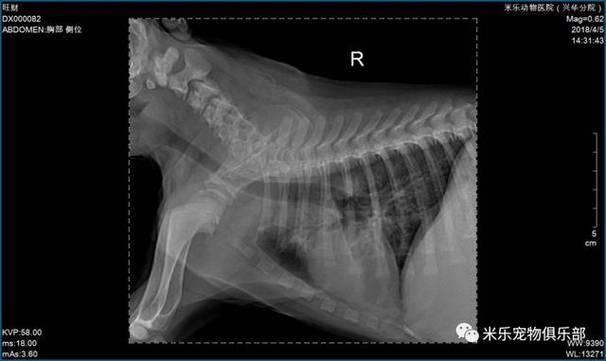

狗狗支气管肺炎多久能治愈 狗狗支气管肺炎治疗为7『1』4天左右。犬支气管炎初期会出现剧烈干咳,之后变成轻度湿性咳嗽,常伴有黏液脓性鼻液的症状;严重时更会出现出痉挛性咳嗽,这种请况病犬会很难受。狗狗支气管肺炎可能的原因比较多,如病毒、寄生虫、细菌以及支原体等引起的肺炎。

狗狗支气管肺炎的治疗周期通常为714天左右。具体治愈时间受以下因素影响:病情严重程度:在病情不是很严重的情况下,狗狗可能一周左右就能见到好转。病因:狗狗支气管肺炎可能由病毒、寄生虫、细菌以及支原体等多种原因引起,不同病因的治疗周期可能有所不同。